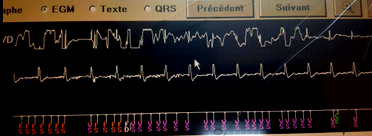

Il s’agit d’un patient âgé de 48 ans, sans antécédents familiaux de mort subite, hospitalisé en Mai 2015 dans les suites d’une syncope vraie survenant à la mosquée lors de la prière. Il n’y avait pas d’arguments en faveur d’une hypotension orthostatique, ni en faveur d’une syncope vaso-vagale. L’examen à l’époque avait retrouvé un aspect d’un syndrome de Brugada type 1 induit par l’Ajmaline avec par ailleurs un QRS fragmenté. L’échographie cardiaque était normale. La stimulation ventriculaire programmée avait induit une TVNS mal tolérée. La recherche de mutation du SCN 5A était négative. Le diagnostic de syndrome de Brugada a été retenu avec une syncope d’origine rythmique et le patient a bénéficié de l’implantation d’un DAI mono-chambre de marque Medtronic. Aucune thérapie n’a été délivrée et aucun trouble de rythme n’a été noté jusqu’au mois d’Avril 2019 où le patient a reçu 21 chocs consécutifs survenant le soir au repos. Voici le récapitulatif des évènements avec un des tracés endo-cavitaires

Quel diagnostic reteniez-vous ?